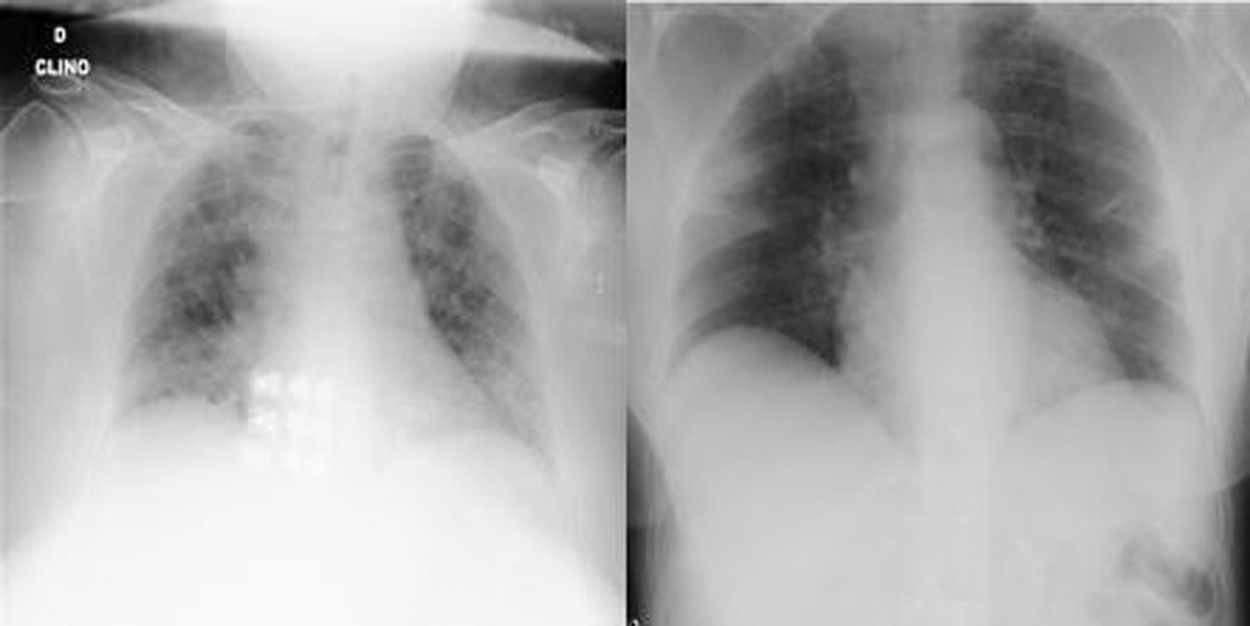

Figs. 1 and 2 show samples of normal and COVID-19 X-ray images, respectively.

Figure 1: Two normal X-ray images

Figure 2: Two COVID-19 X-ray images